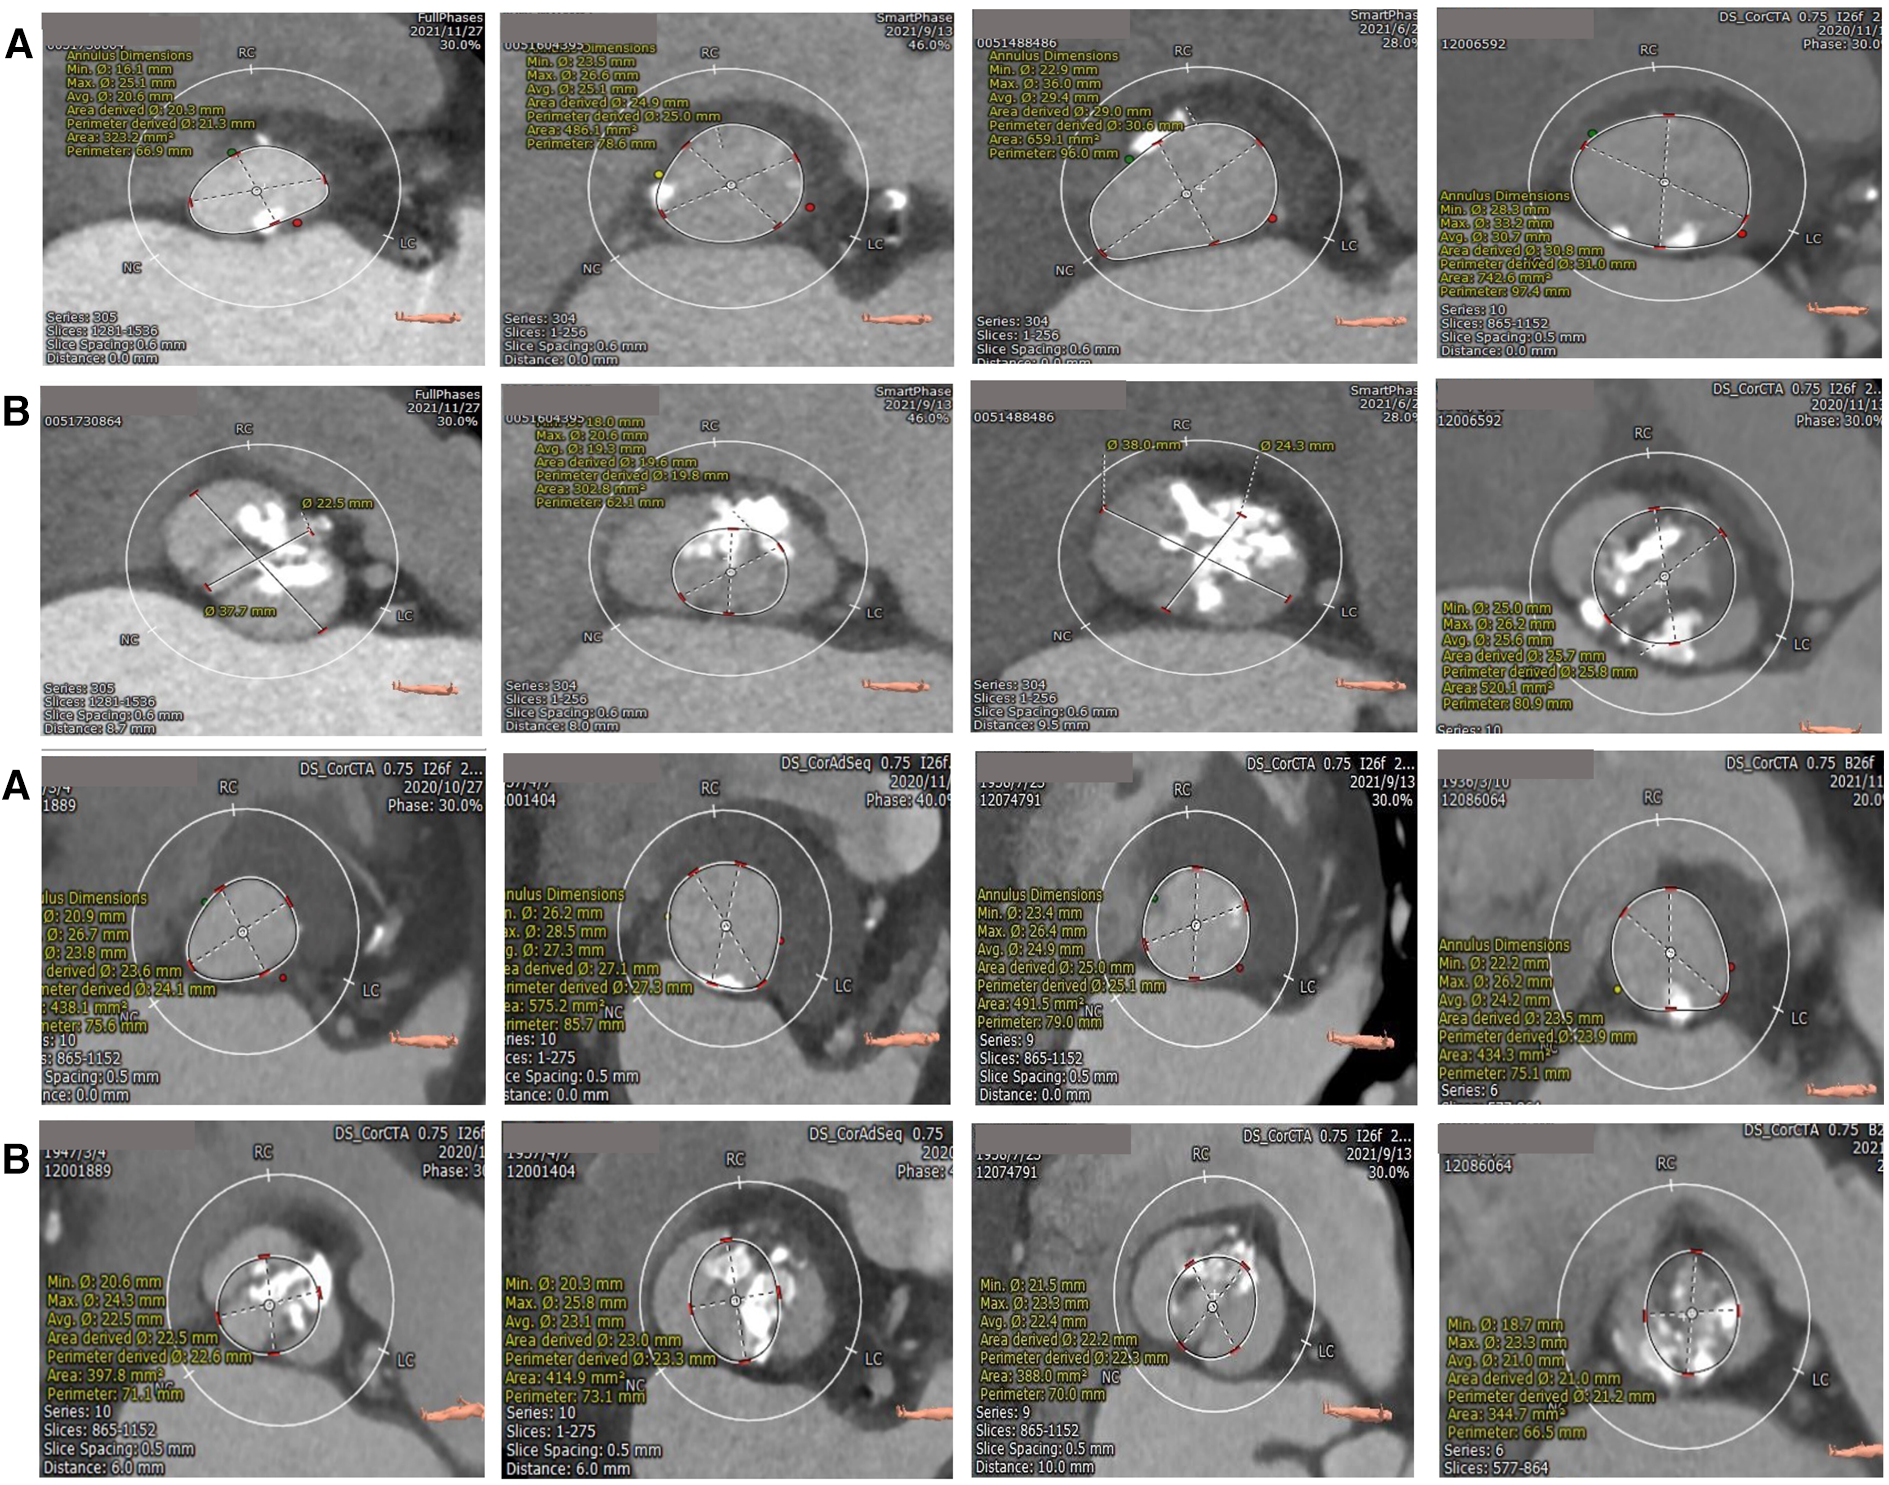

Univariate logistic regression analysis, including age, STS score, and other factors, showed that bulky calcification at the commissure and the ellipticity index of the aortic root correlated with device success. Variables with p-values < 0.1 on univariate analysis were entered into multivariate logistic regression models. Multivariate logistic regression analysis, including bulky calcification at the commissure, the ellipticity index and oversizing ratio as covariates, showed that bulky calcification at the commissure negatively correlated with device success (odds ratio, 0.030, 95% confidence interval 0.003–0.285, p = 0.002) (Table 4). A total of 8 patients had bulky calcification at the commissure, with calcification mostly observed 6–8 mm above the annulus (Figure 1).

Figure 1

Calcification distribution of annulus (A) and bulky calcification at the commissure (B) superior and inferior are the same patients. The bulk calcification appeared primarily on the plane 6–8 mm above the annulus.

Type-0 BAV is different from type-1 BAV in many aspects. The absence of a raphe and 2 symmetric sinuses means that with TAVR in type-0 BAV, the prosthetic valve is rarely pushed to one sinus. In our study, the presence of bulky calcification was found to be an independent risk factor for device failure. The reasons may be as follows: The bulky calcification causes displacement or insufficient expansion of the prosthetic valve or poor adherence to the aortic wall, thus resulting in the use of a second valve, moderate-to-severe paravalvular regurgitation, or a high postoperative transvalvular pressure gradient. PVR is associated with an increased 5-year risk of mortality, and insufficient expansion of the prosthetic valve may impact device durability (18, 19). Probably due to the shear stress of the blood, we found that calcification was mainly present at the free edge of the leaflets, in a linear pattern. An elliptical aortic root may also lead to underexpansion of the prosthetic valve, thereby leading to the presence of paravalvular regurgitation and high transvalvular gradients. However, in multivariate logistic regression analysis, the elliptical index showed no statistical significance.